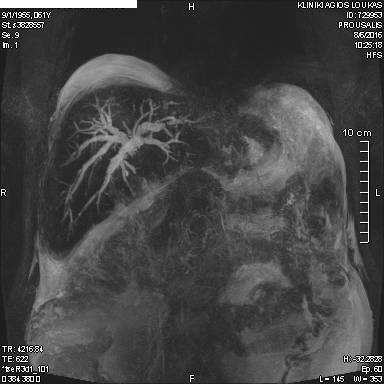

Στα πλαίσια διερεύνησης του πρωτοεμφανιζόμενου διαβήτη, υποβλήθηκε σε μαγνητική τομογραφία άνω κοιλίας (MRI/MRCP) που ανέδειξε μια συμπαγή μάζα στην κεφαλή του παγκρέατος, διαμέτρου περίπου 2εκ και μεγάλη διάταση του παγκρεατικού πόρου.

Ο ασθενής υποβλήθηκε σε ενδοσκοπικό υπέρηχο που έδειξε μια υποηχοϊκή μάζα διαμέτρου 21 χιλιοστών, με σαφή όρια, στην παγκρεατική κεφαλή και μεγάλη διάταση του χοληδόχου πόρου και του παγκρεατικού πόρου (διάμετρος 12 χιλιοστά).

Μάζα παγκρέατος στη μαγνητική τομογραφία

ΜRCP: διάταση παγκρεατικού πόρου